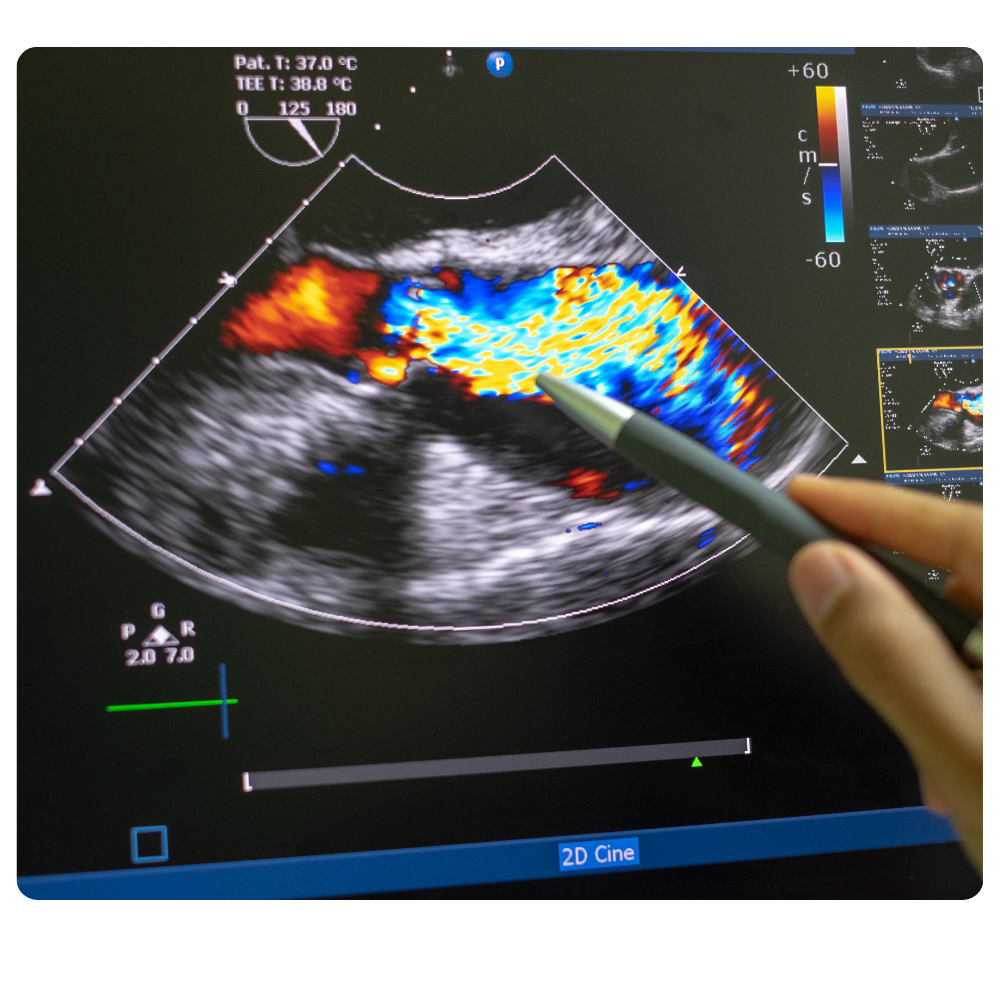

El ecocardiograma + Doppler Color es una herramienta de diagnóstico fundamental que utiliza ultrasonido para crear una imagen detallada y en tiempo real de su corazón. Este estudio nos permite evaluar la estructura, el funcionamiento y el movimiento de las válvulas y el músculo cardíaco.

Además, el sistema Doppler añade información vital al analizar y visualizar el flujo de la sangre a través de las cavidades y vasos principales del corazón. Con este examen de alta precisión, el Dr. Canseco puede obtener un diagnóstico completo de la salud de su corazón.